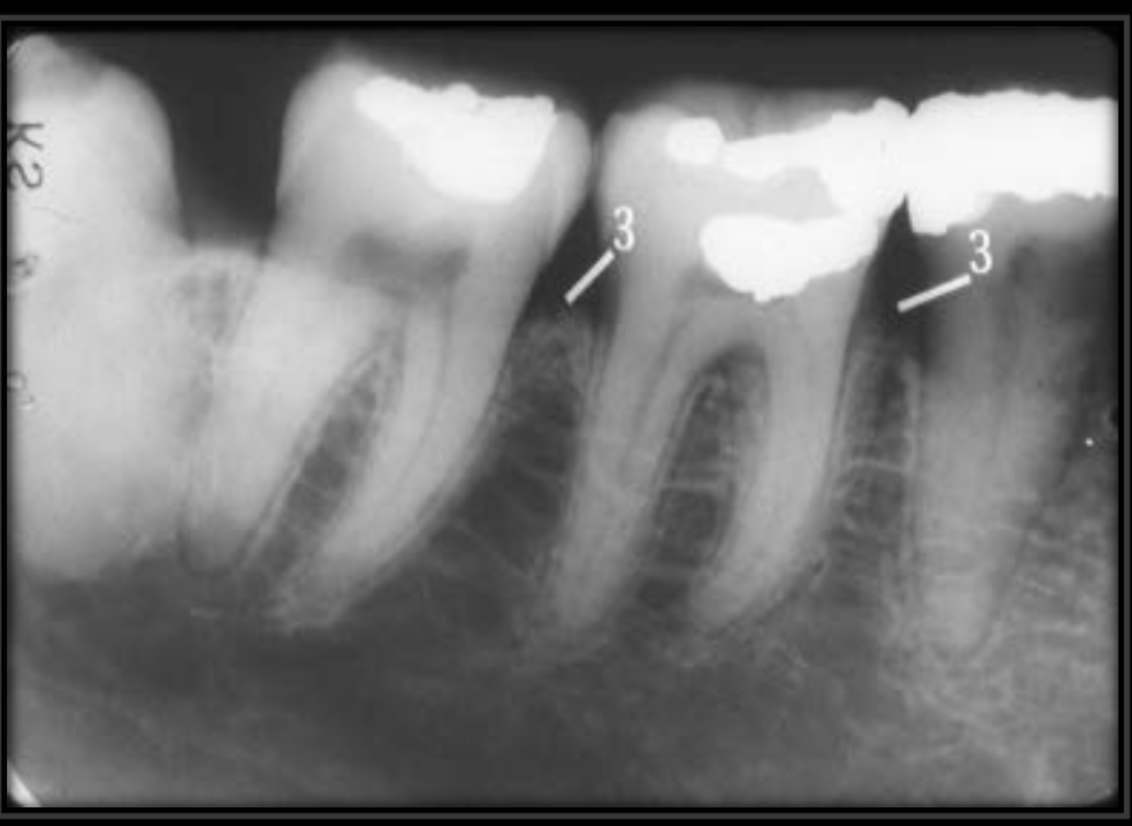

How does the external oblique ridge present in a radiograph?

Always the highest opaque line of the mandible that follows the contour of the jaw.

How does the internal oblique ridge present in a radiograph?

The second highest opaque line on the mandible that follows the contour of the jaw. Will always be below the external oblique ridge